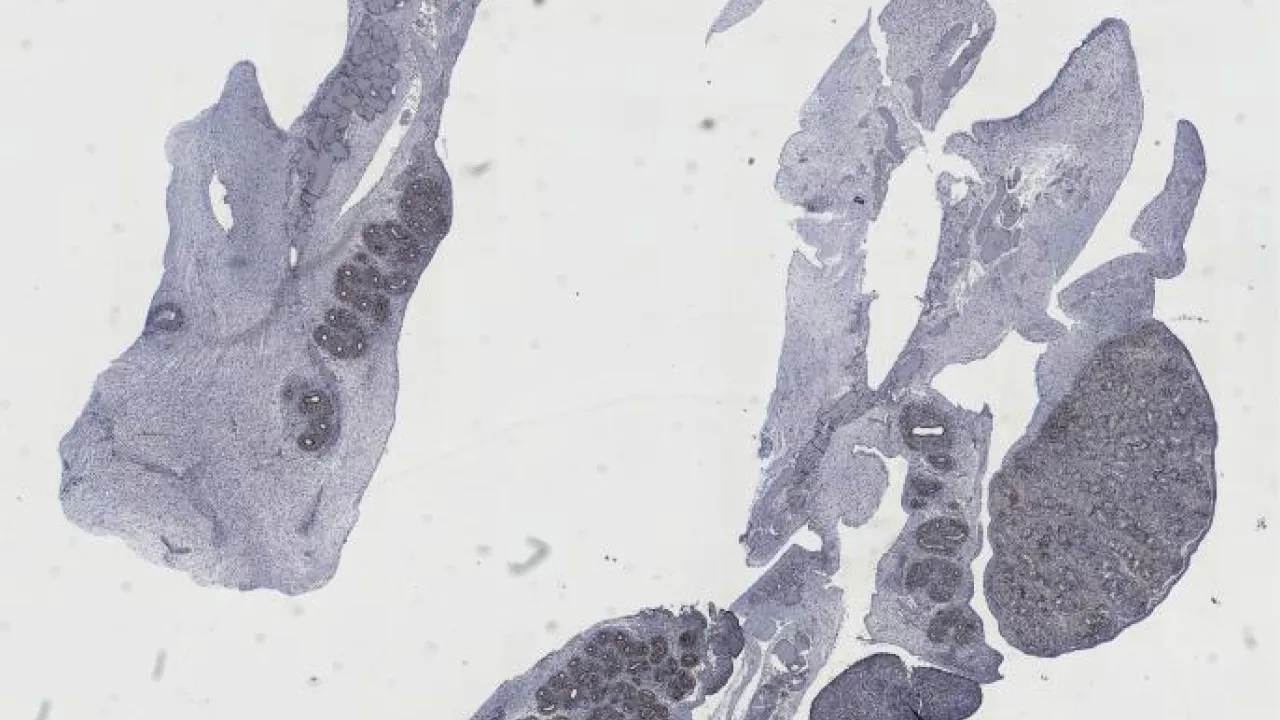

Lower Urinary Tract and Male Genital System

Subscribe to Lower Urinary Tract and Male Genital System